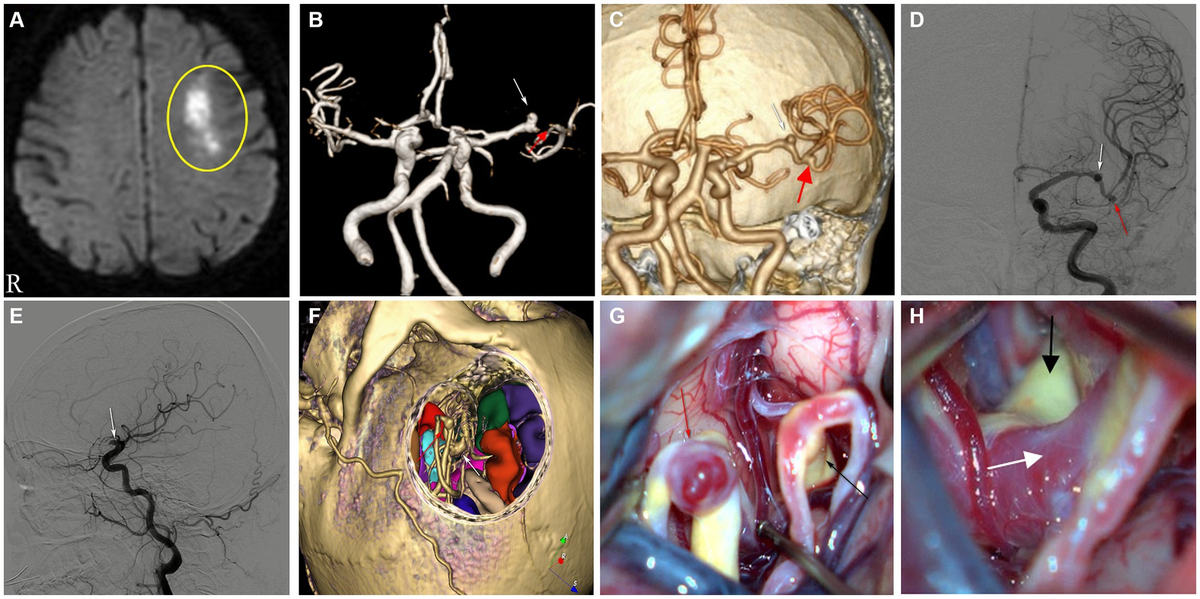

Fusiform vertebral artery aneurysms involving the posterior

Fusiform vertebral artery aneurysms involving the posterior

Fusiform vertebral artery aneurysms involving the posterior,

Fusiform vertebral artery aneurysms involving the posterior, Frontiers | False positive angiographic aneurysm of the,

Frontiers | False positive angiographic aneurysm of the, Brain arteriovenous malformations of the middle cerebral,

Brain arteriovenous malformations of the middle cerebral, Brain Arteriovenous Malformations - Neuroimaging Clinics

Brain Arteriovenous Malformations - Neuroimaging Clinics